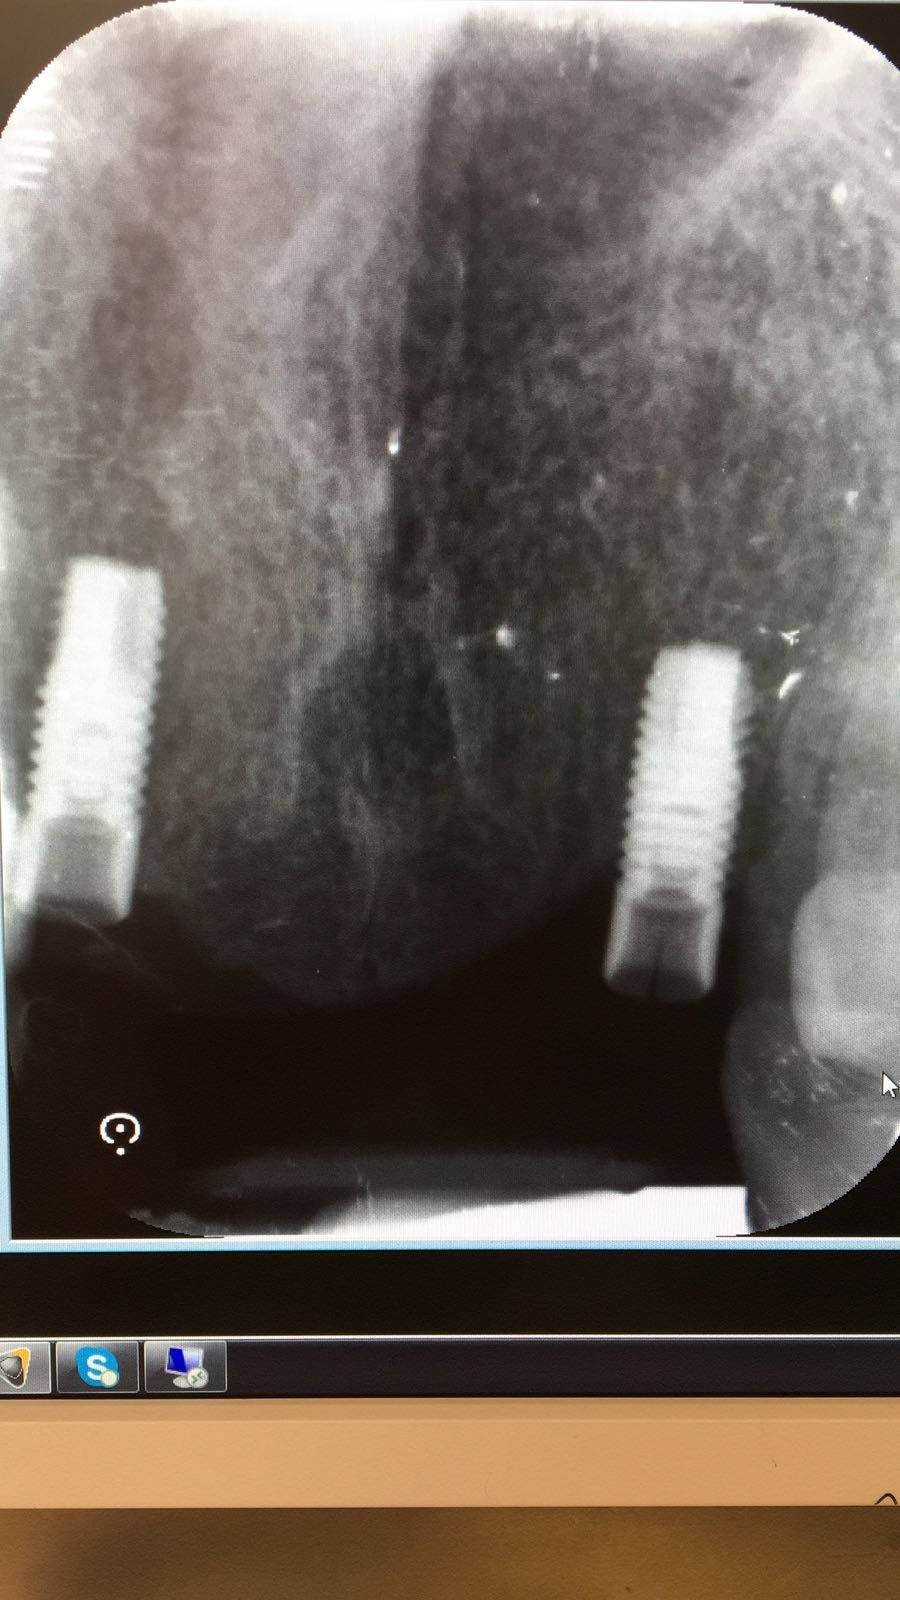

Implante en 25 sin identificar

Alguien podria ayudarnos a identificar el implante y el pilar de la rx. Muchas gracias!!!!